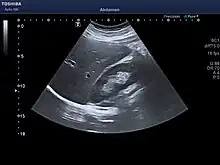

Microscopic anatomy

Microscopically, each liver lobe is seen to be made up of hepatic lobules. The lobules are roughly hexagonal, and consist of plates of hepatocytes, and sinusoids radiating from a central vein towards an imaginary perimeter of interlobular portal triads.[22] The central vein joins to the hepatic vein to carry blood out from the liver. A distinctive component of a lobule is the portal triad, which can be found running along each of the lobule's corners. The portal triad consists of the hepatic artery, the portal vein, and the common bile duct.[23] The triad may be seen on a liver ultrasound, as a Mickey Mouse sign with the portal vein as the head, and the hepatic artery, and the common bile duct as the ears.[24]

The diagnosis of liver disease is made by liver function tests, groups of blood tests, that can readily show the extent of liver damage. If infection is suspected, then other serological tests will be carried out. A physical examination of the liver can only reveal its size and any tenderness, and some form of imaging such as an ultrasound or CT scan may also be needed.

Sometimes a liver biopsy will be necessary, and a tissue sample is taken through a needle inserted into the skin just below the rib cage. This procedure may be helped by a sonographer providing ultrasound guidance to an interventional radiologist.[69]